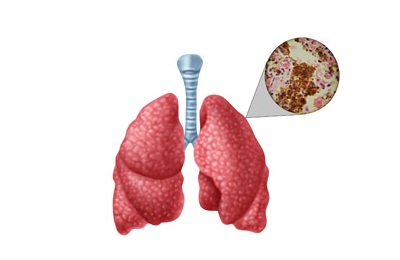

Основним джерелом туберкульозної інфекції є людина, хвора на туберкульоз легень, яка виділяє мікобактерії туберкульозу з мокротинням при кашлі, чханні та розмові. Також, заразитися можна через вживання молока від інфікованих або хворих на туберкульоз корів. Зараження контактно-побутовим шляхом, зазвичай, відбувається при зіткненні людини із забрудненими мокротою хворого предметами (одяг, білизна, рушник, посуд, зубна щітка, носовичок тощо). Найбільша небезпека – від людей, які хворіють на відкриту форму туберкульозу (в їх мокроті знаходиться багато туберкульозних паличок).

Основним джерелом туберкульозної інфекції є людина, хвора на туберкульоз легень, яка виділяє мікобактерії туберкульозу з мокротинням при кашлі, чханні та розмові. Також, заразитися можна через вживання молока від інфікованих або хворих на туберкульоз корів. Зараження контактно-побутовим шляхом, зазвичай, відбувається при зіткненні людини із забрудненими мокротою хворого предметами (одяг, білизна, рушник, посуд, зубна щітка, носовичок тощо). Найбільша небезпека – від людей, які хворіють на відкриту форму туберкульозу (в їх мокроті знаходиться багато туберкульозних паличок).

- кашель є постійним симптомом туберкульозу легенів. На початку хвороби кашель сухий, наполегливий, загострюється вночі та вранці. При подальшому розвитку хвороби він стає вологим з виділенням мокроти. Присутність кашлю більш ніж 3 тижні має насторожити і стати причиною звернення до лікаря;

- кровохаркання – одна з важливих ознак туберкульозу легенів, яка з’являється при інфільтративному туберкульозі, а також при інших формах цієї хвороби;